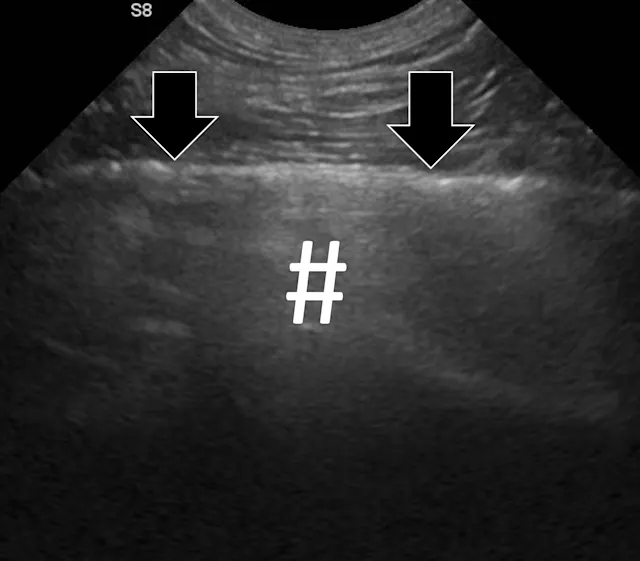

FIGURE 2A

Abdominal ultrasound of a 3-year-old neutered male crossbreed dog with a surgically confirmed mechanical pyloric outflow obstruction. A homogeneously hypoechoic potato (asterisk) is present in the pylorus and completely visible due to its similar acoustic impedance as the surrounding soft tissues. There is transition from gas in the gastric lumen to the foreign body (white arrow). The remainder of the gastric lumen (pound sign) is not visible due to gas (black arrows) causing a hyperechoic surface with reverberation artifact.